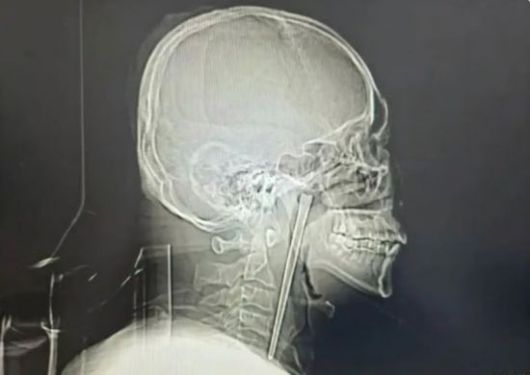

남성의 목에 박힌 금속 젓가락. 바이두 캡처 |

정밀 검사 결과 A씨가 8년 전 삼킨 금속 젓가락은 입천장 뒤에 위치한 목 안쪽 연구개 부위에 박혀 있었다. 다행히 목 주변 점막은 손상되지 않았고, 성대도 정상적으로 기능했다.